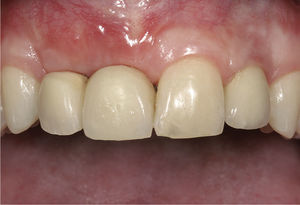

Cinco meses después de la última intervención y de un período postoperatorio sin contratiempos, se reali-zó la preparación definitiva de los dientes pilares. Para cubrir de forma segura los pilares dorados se fresaron sendas estructuras para la corona y el puente en cerá-mica de óxido de zirconio (figs. 17 y 18). A finales de 2008, un año y medio después de iniciar el trata-miento, se pudo conectar la prótesis definitiva y dar el alta a una paciente feliz que mostró con una sonrisa na su gran satisfacción por los resultados consegui-dos (figs. 19 y 20). La figura 21 muestra la sonrisa de la paciente un año después de la finalización del trata-miento.